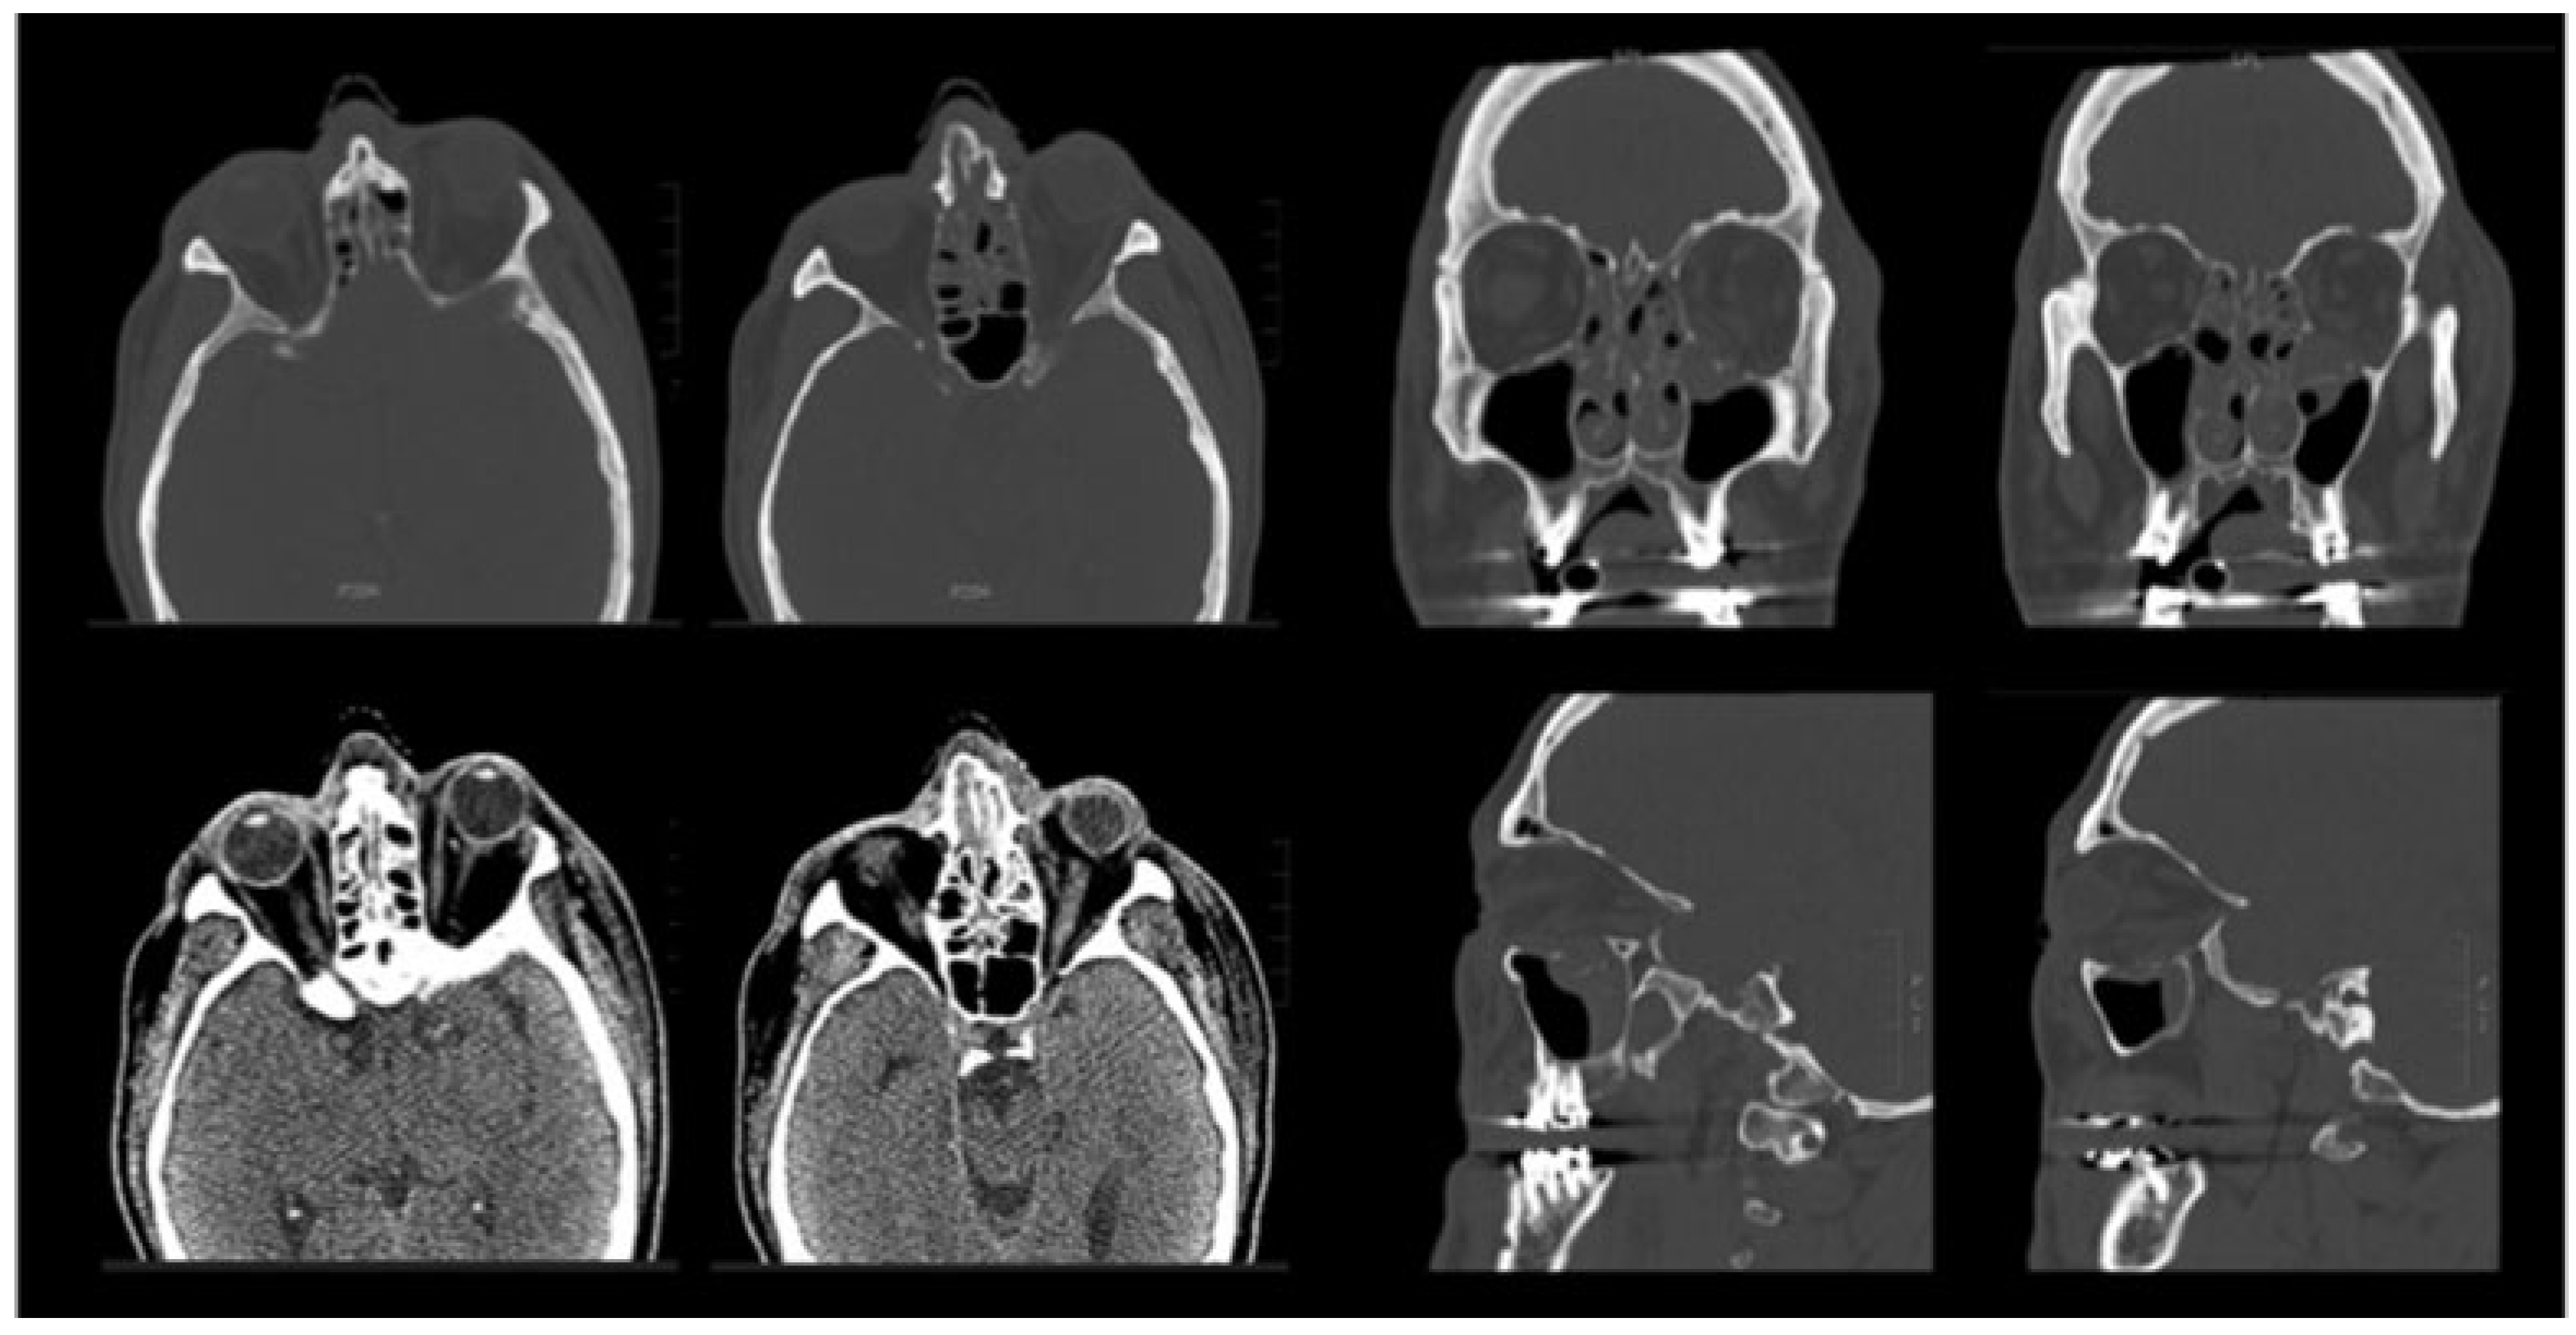

The patient was subsequently extubated and visual acuity was noted to be intact, with pupillary light response present before leaving the operating room. A maxillofacial CT was performed immediately postoperatively and demonstrated reconstitution of the orbital volume, with adequate placement of the hardware and no evidence of retrobulbar hemorrhage or impingement of the orbital apex by the hardware (Figure 3). Of note, there were no documented episodes of hypo- or hypertension intraoperatively.

Figure 3. Immediate postoperative computed tomography. Axial (top row), coronal (middle row), and sagittal (bottom row) images show reconstruction of the orbital floor with a titanium mesh implant. The orbital volume is almost fully restored. There is no evidence of impingement of the hardware on the optic canal and no retrobulbar hemorrhage.